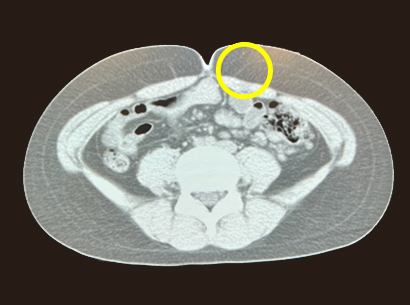

【症例4】 10代男児

発症から6か月間、近医でブロックを受けていた。

一時的な改善は得られるものの再発を繰り返すため当院を受診。CTで疼痛部位に一致して皮神経のようなものが描出された。小切開で皮神経を切除。術後より疼痛の消失を自覚。翌日に退院。